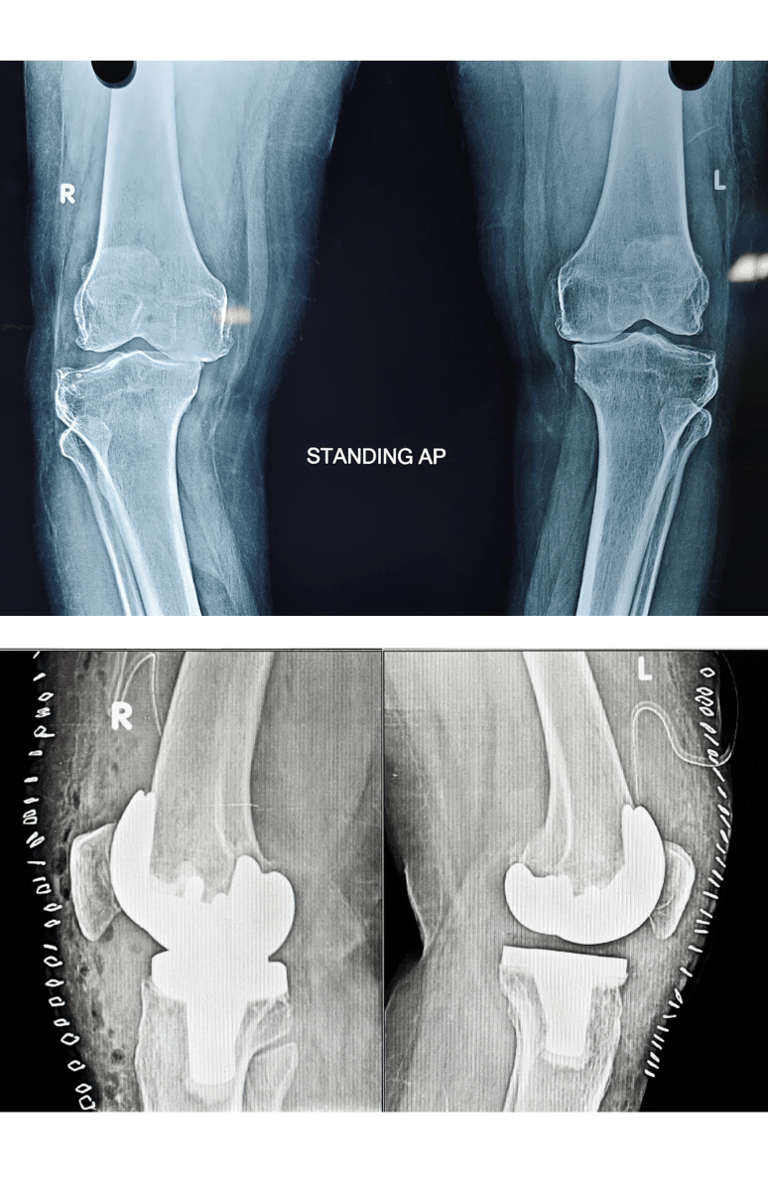

Sivam Hospital – Advanced Knee Replacement in Chennai

At Sivam Hospital, we specialize in advanced joint replacement surgeries to relieve pain, restore mobility, and enhance quality of life. Our expert orthopedic team uses modern techniques and state-of-the-art facilities to ensure safe procedures and faster recovery.

Expertise in Knee, Uni Knee ,Revision Total Knee Replacement & Total Knee Replacement (TKR)

Knee Replacement – Effective treatment for severe Osteoarthritis, Rheumatoid arthritis, secondary arthritis, inflammatory arthritis and joint damage helping patients regain pain-free movement.

Uni Knee Replacement – A minimally invasive partial knee replacement procedure that preserves healthyportion of the joint and tissue while ensuring quicker recovery.

Total Knee Replacement (TKR) – Comprehensive surgical care to replace the entire knee joint, offering lasting pain relief, deformity correction, improved gait and function.

Revision Total Knee Replacement– Specialized surgery to correct or replace the failed knee implants due to infection or trauma restoring stability and improving function.